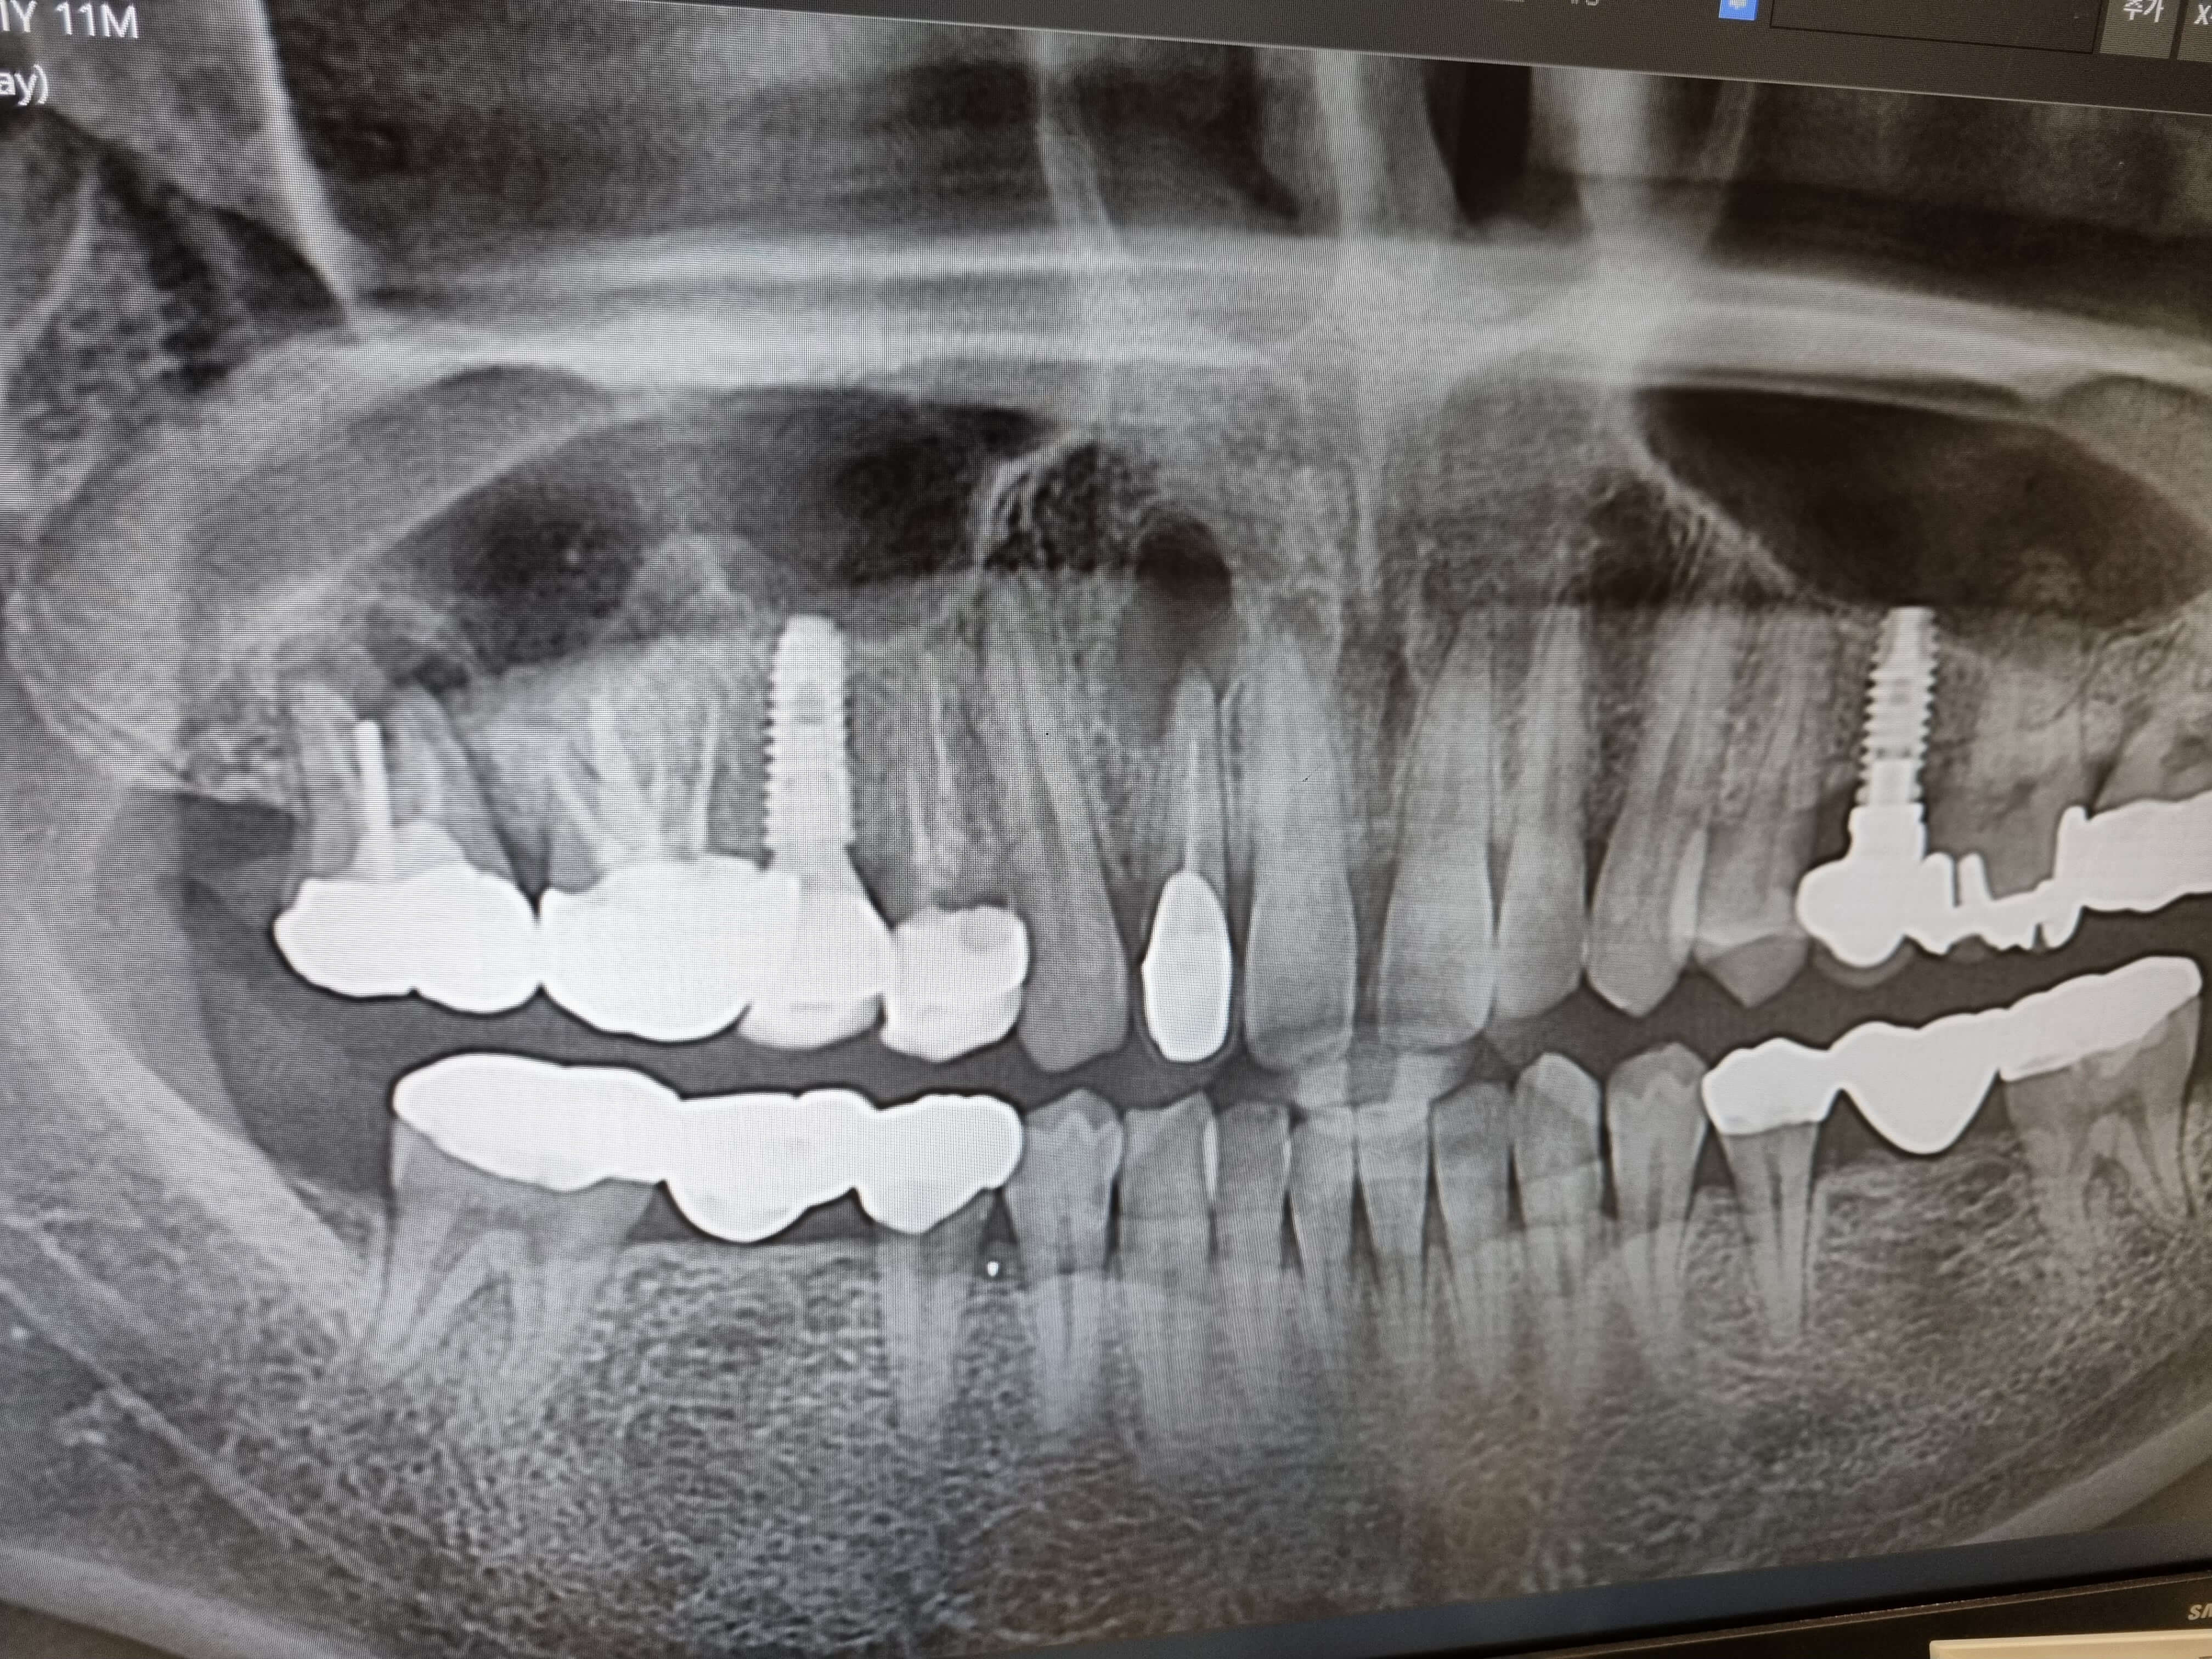

위 사진을 보시면 뼈가 뚤려 있습니다. 이것은 앞니 염증이 오래되다 보니 뼈를 녹여버리게 되었네요. 이것을 어떻게 치료해야 할지 치과선생님께 여쭈어 보니 해당 앞니 크라운을 사용할수 없으니 먼저 신경치료부터 해본다고 합니다.

염증 범위가 넓어 신경치료로 염증이 나아지지 않으면, 잇몸절단을해서 염증을 하나하나 다 긁어 낸다고 하네요. 이때 치아 뿌리를 자르고 잘살려 치료가 되면 새로운 크라운 정도로 하면 되는데 이것도 잘안되면 결국 뚤린 뼈에 치조골 이식을 해서 임플란트를 시행해야 한다고 합니다.

▣ 치아 전체를 검사한 결과

새로운 치과를 처음 방문하면 현재 치아상태를 알기위해 전부 사진을 찍고, 상황에 따라 CT까지 찍습니다. 저같은경우 2군데의 치아가 염증이 차있는걸로 확인되었고, 앞니쪽이 심해서 CT를 찍어본결과 참담한 결과가 나왔네요.

또한 오른쪽 임플란트 옆에 해넣은 크라운은 뿌리에서 염증이 발생해서 아깝지만 발치를 하는게 옳다고 여겨 그날 바로 발치를 했습니다. 이글을 적고 있는 오늘 발치해서 아프네요.